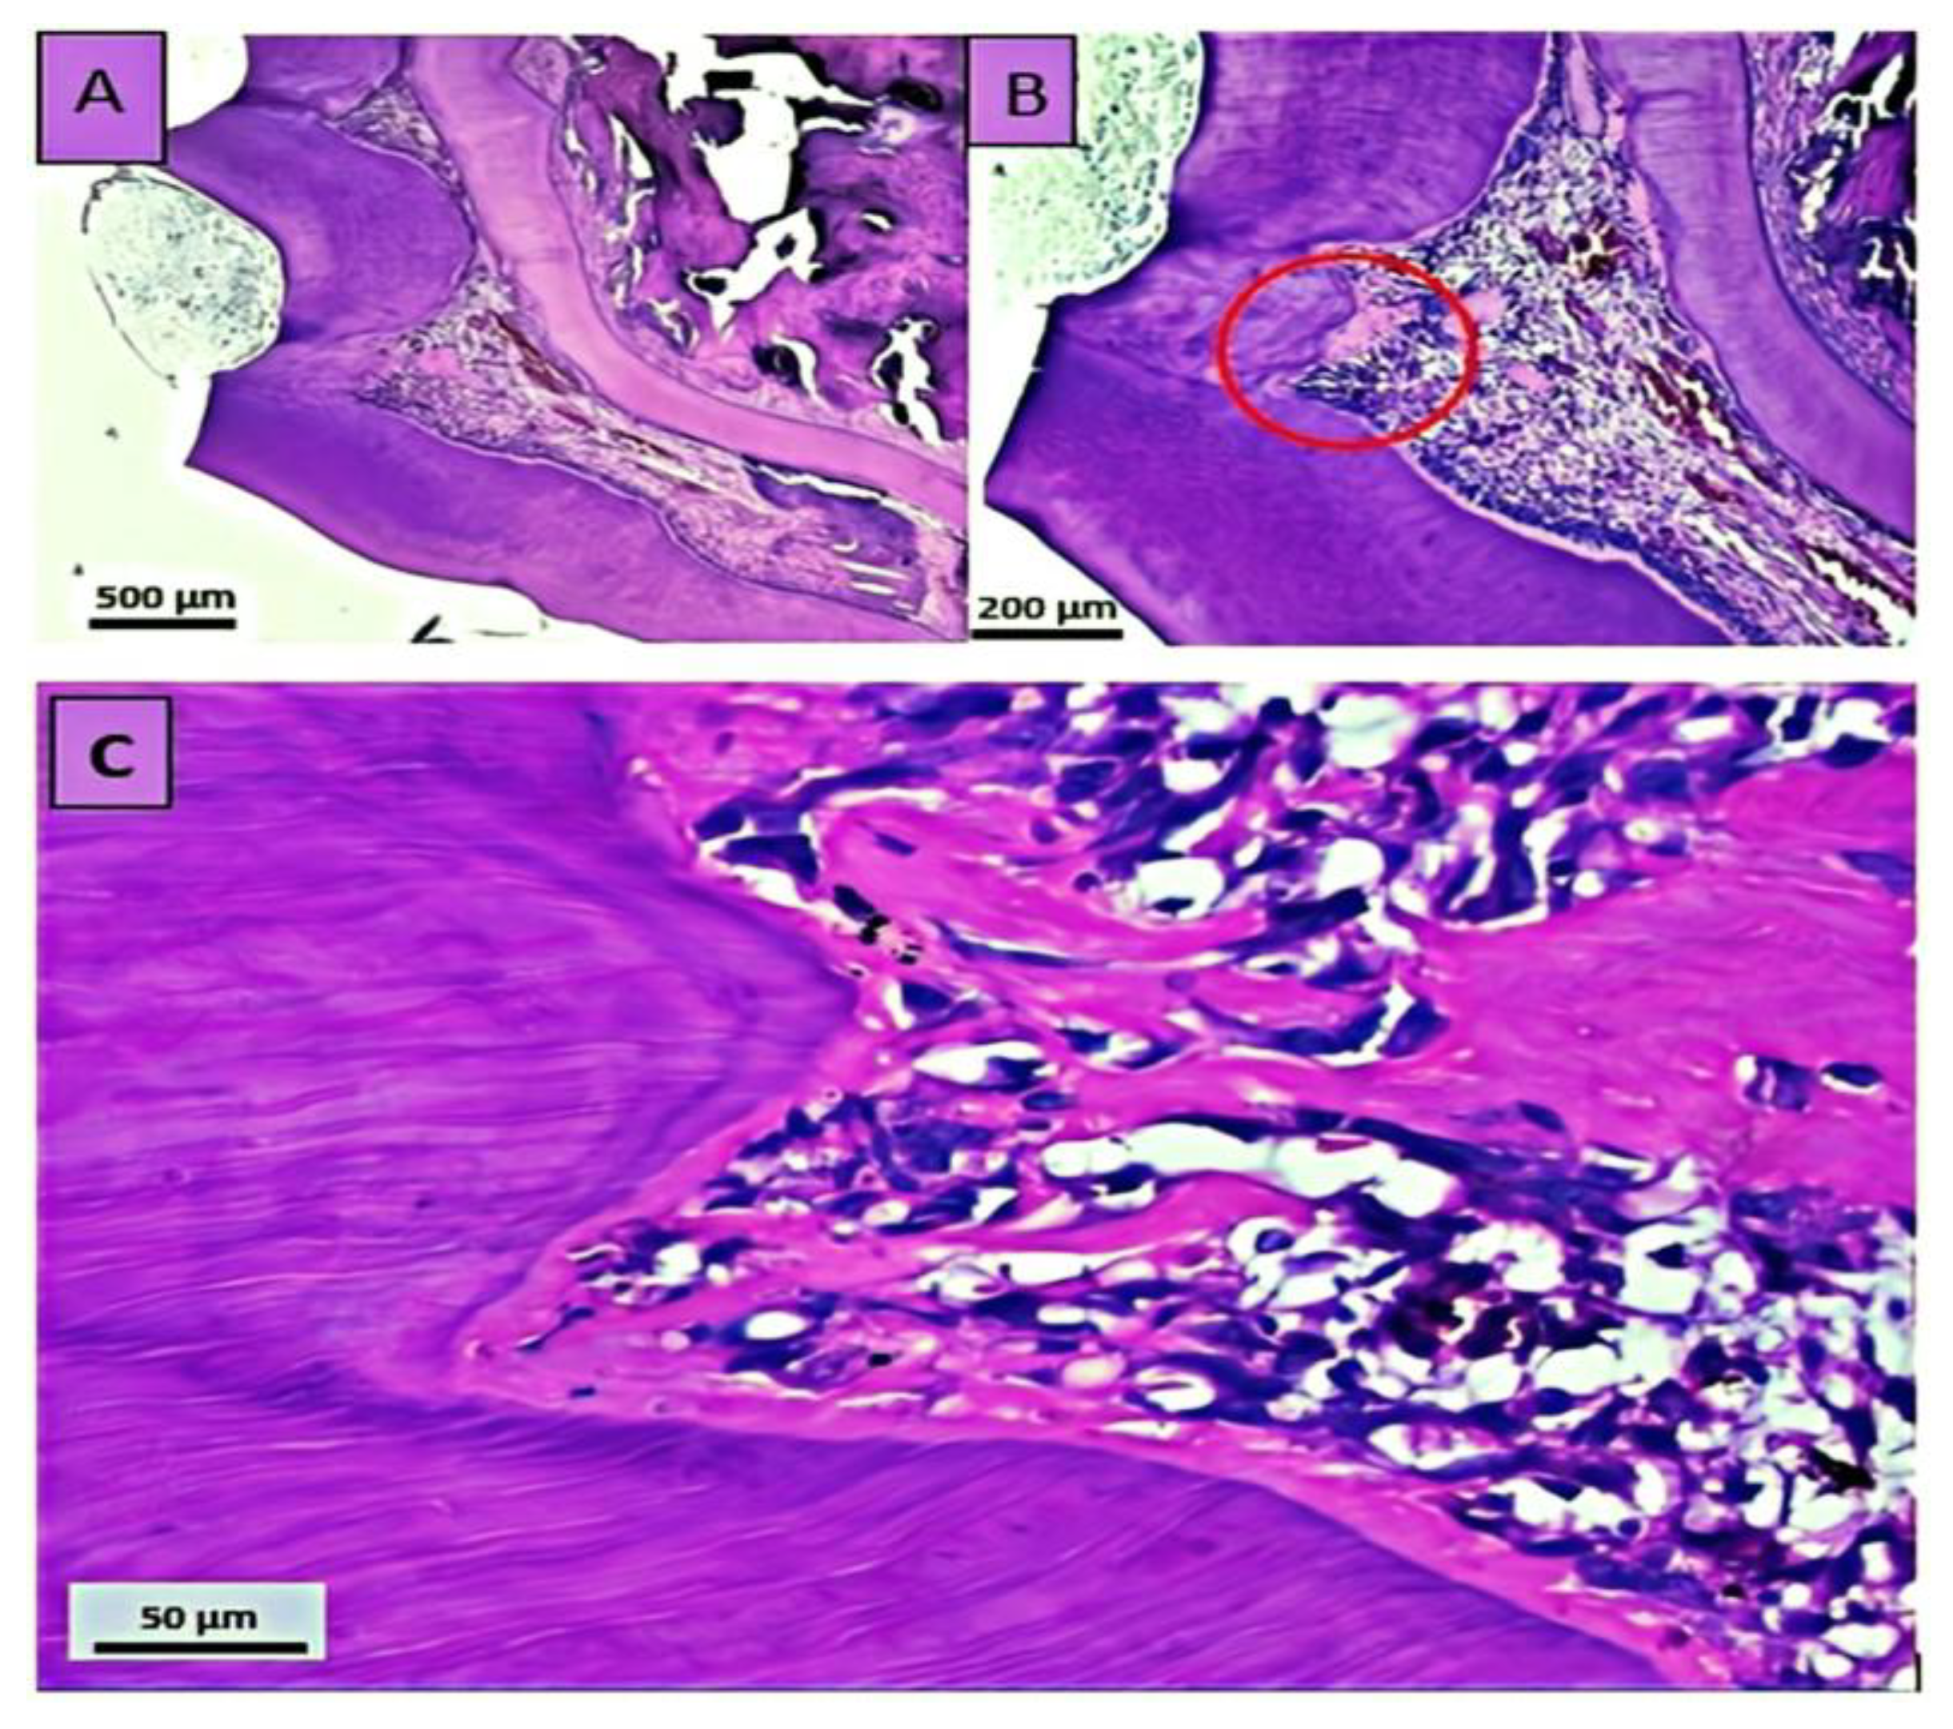

3.1.4. Residual Dentin Thickness and Tertiary Dentin Formation

| D | Tertiary dentin deposition |

| 0 | No or very mild tertiary dentin deposition (0–49 µm = Grade 0) |

| 1 | Initial tertiary dentin deposition extending to not more than one-half of the cavity floor (50–99 µm = Grade 1) |

| 2 | Moderate tertiary dentin deposition extending to more than one-half of the cavity floor but not completely closing the cavity floor (100–249 µm = Grade 2) |

| 3 | Intense tertiary dentin deposition, extending entirely along the cavity floor (250–500 µm = Grade 3) |